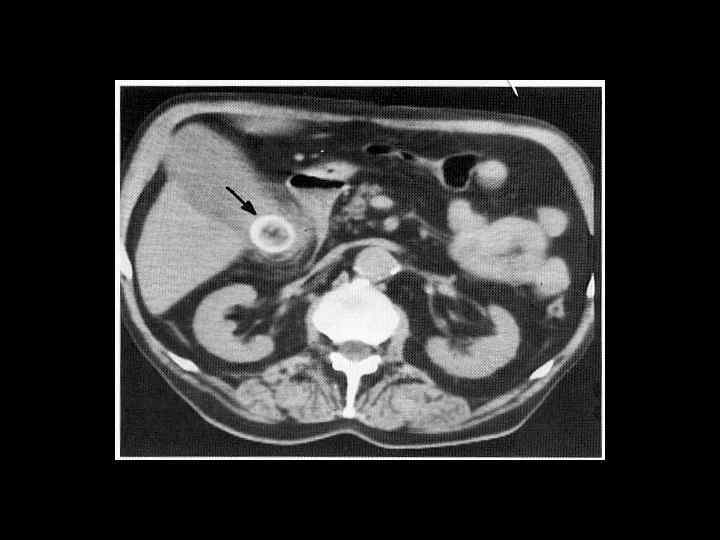

АКТУАЛЬНЫЕ ВОПРОСЫ РЕНТГЕНОЛОГИИ ЛУЧЕВАЯ ДИАГНОСТИКА ЗАБОЛЕВАНИЙ ЖЕЛЧЕВЫДЕЛИТЕЛЬНОЙ СИСТЕМЫ Карциномы желчного пузыря и желчного протока КТ семиотика